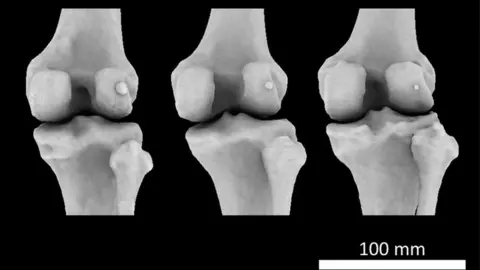

Imperial College LondonA little bone in the knee scientists thought was being lost to evolution seems to be making a comeback, say experts from Imperial College London.

Imperial College LondonWhy do some of us have it?